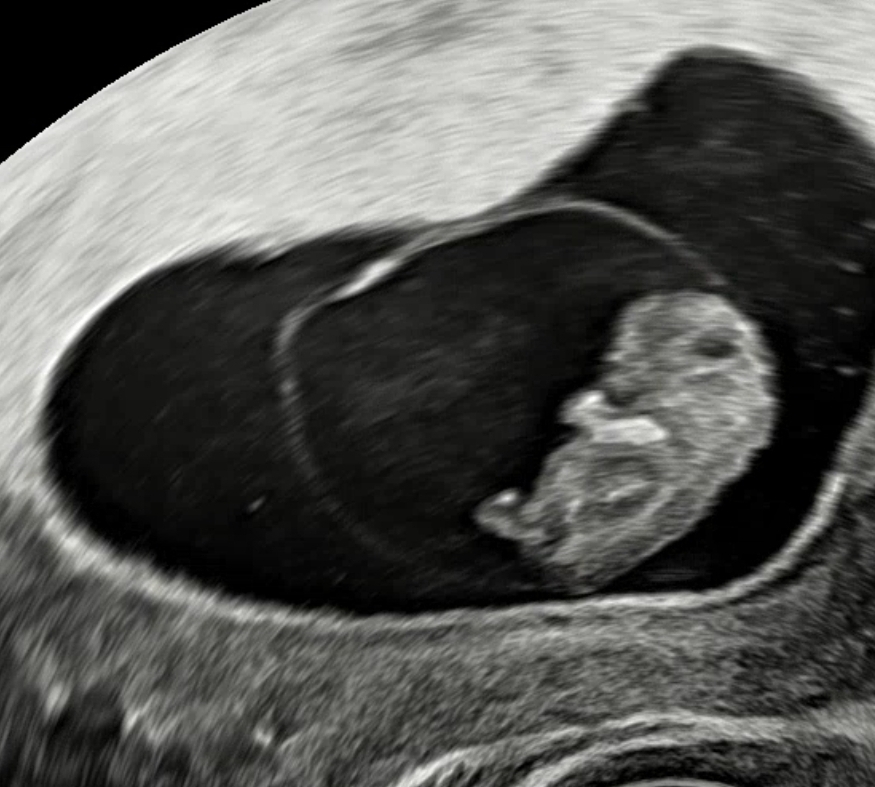

8주5일차 젤리곰

8주 5일차 초음파 봤어요 예쁜 젤리곰은 아니지만 팔 다리가 생겼지요~아직 내 안에 또 다른 생명이 있다는게 믿기지는 않지만 신기해요~

저도 쌤이 팔이랑 다리라고 하는데 ㅋ너무 앙증맞아서 미소가 절로 나오더라구요 ㅋㅋ

팔다리 너무 귀여워용!!ㅎㅎ